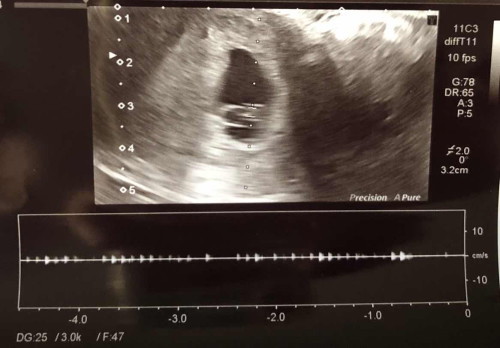

สวัสดีแม่ๆ ตอนนี้เรา ตั้งครรภ์ 6 w วันก่อน ไปอัลตราซาวด์มาค่ะ ขนาดตัวอ่อนประมาณ 4mm อัลตราซาวด์ผ่านช่องคลอด เห็นตัวและหัวใจน้องกระพริบๆ แต่พอวัดคลื่นหัวใจน้อง คุณหมอแจ้งว่า มันเบามากเลย และให้มาอัลตราซาวด์ติดตามผลอีก 4 สัปดาห์ อยากปรึกษาแม่ๆ ที่มีประสบการณ์คล้ายๆกัน ว่า มีโอกาสที่น้องจะรอดเป็นปกติมั้ยคะ #ขอบคุณคำตอบค่ะ

บ้านนี้ไปอัลตราซาวด์พร้อมฝากตอน7w เห็นตัวพร้อมหัวใจกระพริบ หมอก็จะให้ฟังเสียงหัวใจ แต่หมอบอกยังฟังเสียงหัวใจไม่ได้ ขนาดตัวเล็กเท่าอายุครรภ์4-5w ขนาดแค่2.66mm หมอนัดหลังจากนั้น4สัปดาห์เหมือนกัน แต่ไม่ได้แจ้งว่าผิดปกติหรืออะไร